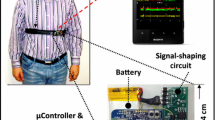

Sazonov, E. S., S. A. Schuckers, P. Lopez-Meyer, O. Makeyev, E. L. Melanson, M. R. Neuman, and J. O. Hill. Toward objective monitoring of ingestive behavior in free-living population. Obes. Res., 2009. doi:10.1038/oby.2009.153.

Sazonov, E. S., S. A. Schuckers, P. Lopez-Meyer, O. Makeyev, N. Sazonova, E. L. Melanson, and M. R. Neuman. Non-invasive monitoring of chewing and swallowing for objective quantification of ingestive behavior. Physiol. Meas. 29(5):525–541, 2008.